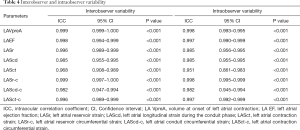

Reproducibility of 4D Auto LAQ

Repeat 4D Auto LAQ measurements of 15 randomly selected participants were taken by the same observers and by another experienced reader 2 weeks later, which allowed for the determination of intra-class correlation coefficients (ICC) as a measure of intra-observer and interobserver agreement. The ICC values ranged from 0.861 to 0.999, (Table 4), indicating good interobserver and intraobserver repeatability.